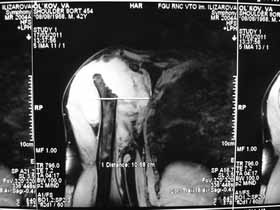

Re: Лизис костей плечевого сустава

Нужна открытая биопсия. будет саркома.

Извиняюсь, что-то фотографии сразу не прошли. сейчас исправимся.